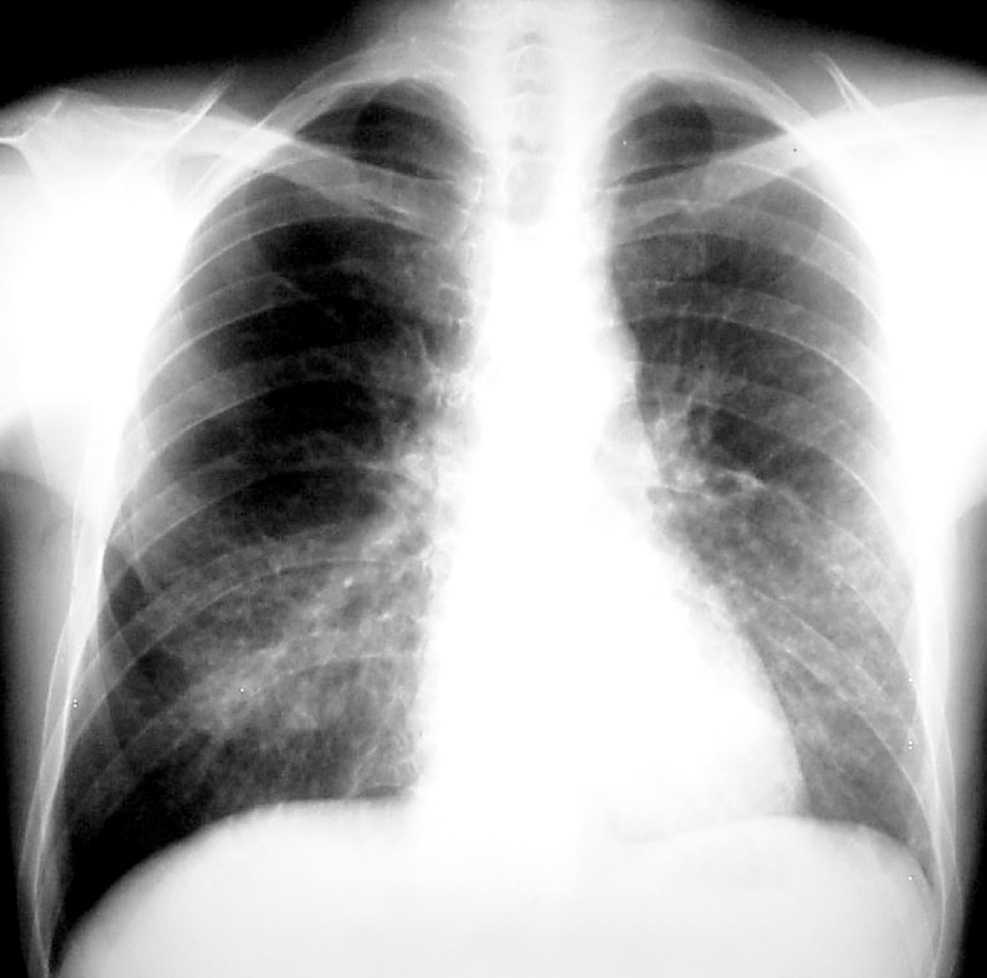

Dentro de las pruebas no invasivas, la tomografía computarizada de alta resolución (TCAR) se ha convertido en un elemento indispensable para establecer un diagnóstico precoz de IFI42-44. Ésta presenta una cinética característica a lo largo del proceso. En el momento del diagnóstico, fase precoz de la infección, el "signo del halo" es el hallazgo más frecuente y se corresponde con una zona de edema o hemorragia de baja atenuación alrededor de una masa o nódulo (figs. 2 y 3). Más adelante, las lesiones se cavitan, aparece aire en su interior y toman aspecto de semiluna42,43.

Figura 2. Signo del halo en aspergilosis invasora.

Figura 3. Signo de la semiluna.